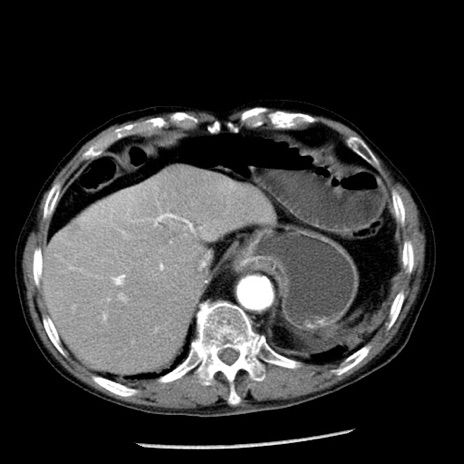

冠状断像

【症例】80歳代男性

【主訴】嘔吐

【現病歴】昨晩2回嘔吐あり、今朝になっても嘔吐あり。来院。

【既往歴】胃潰瘍

【身体所見】意識清明、BT 37.6℃、BP 166/95mmHg、HR 100bpm、SpO2 97%、腹部:平坦・軟、腸蠕動音聴取良好、圧痛なし。

【データ】WBC 21900、CRP 1.46